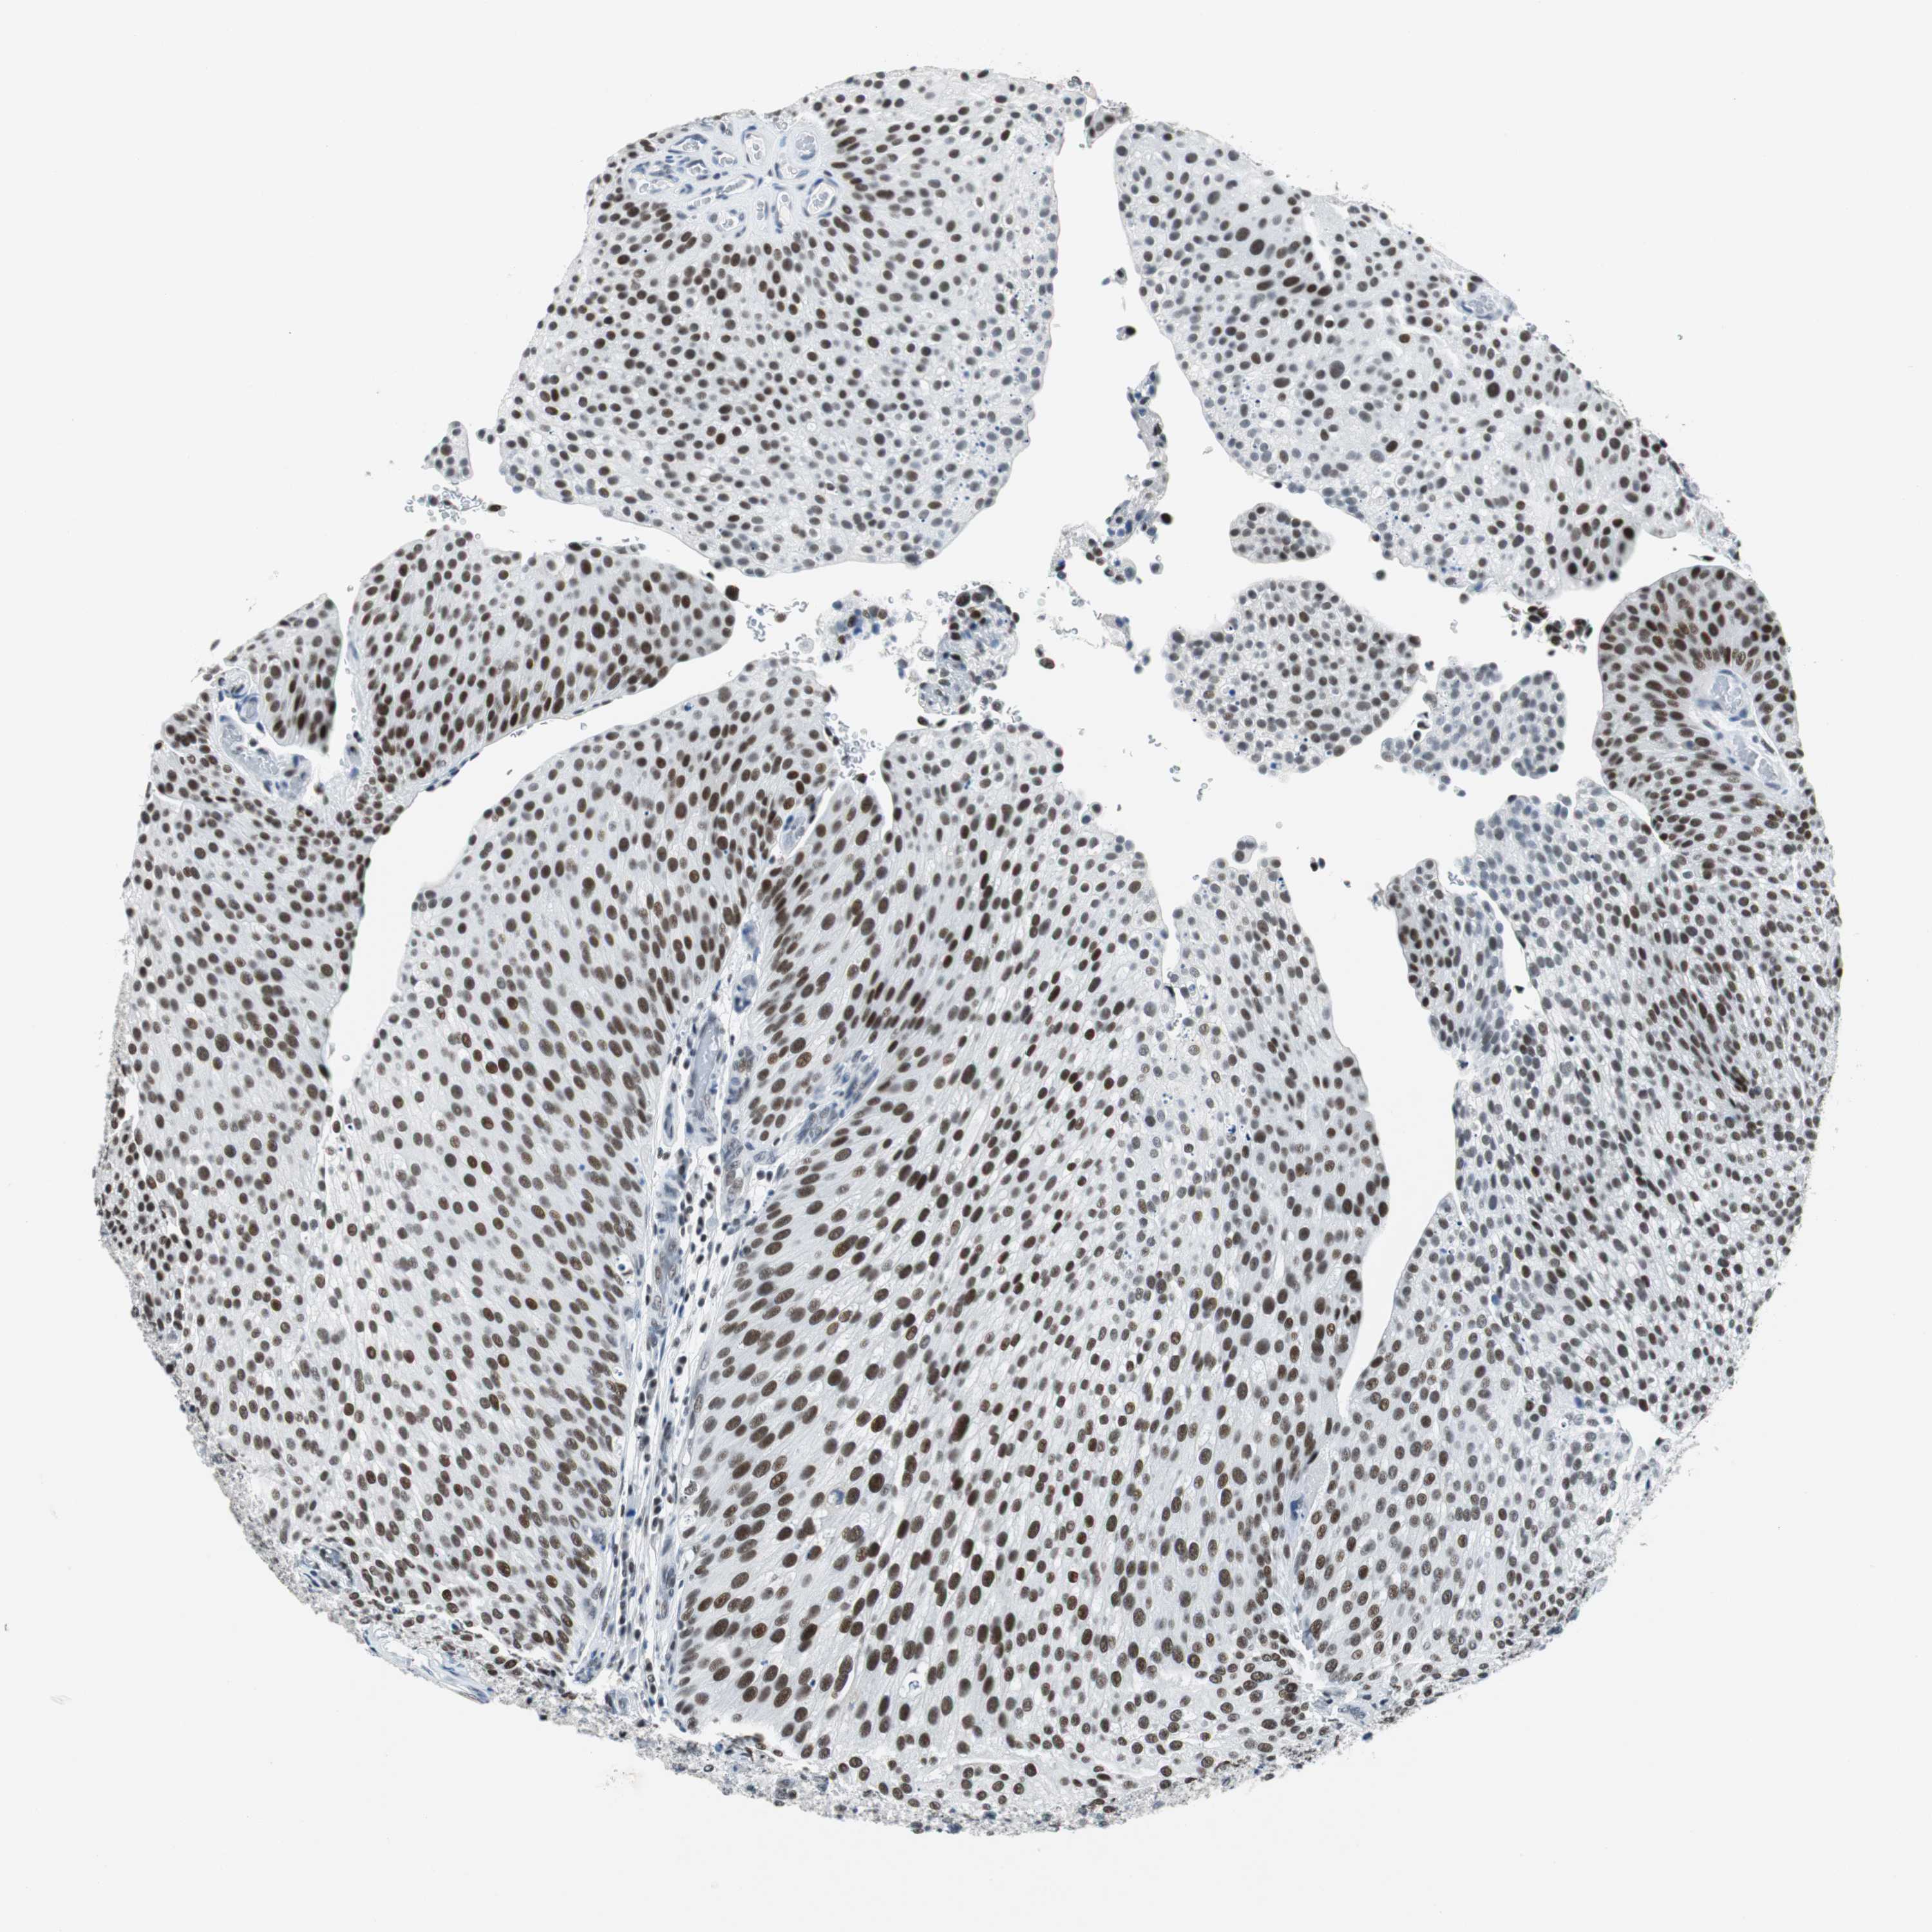

UROTHELIAL CANCER - Protein expressioni

A mouse-over function shows sample information and annotation data. Click on an image to view it in a full screen mode. Samples can be filtered based on level of antibody staining by selecting one or several of the following categories: high, medium, low and not detected. The assay and annotation is described here.

Note that samples used for immunohistochemistry by the Human Protein Atlas do not correspond to samples in the TCGA dataset.

Antibody stainingi

Antibody staining in the annotated cell types in the current human tissue is reported as not detected, low, medium, or high, based on conventional immunohistochemistry profiling in selected tissues. This score is based on the combination of the staining intensity and fraction of stained cells.

Each image is clickable and will lead to virtual microscopy that enables deeper exploration of all samples and also displays staining intensity scores, fraction scores and subcellular localization as well as patient and tissue information for each sample.

Antibody HPA052052

Antibody CAB005583

Antibody CAB072336

Urothelial carcinoma, High grade

Urothelial carcinoma, Low grade

Urothelial carcinoma, NOS